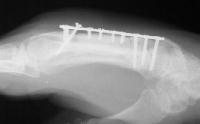

I believed that the nonunion was due to the combined effects of an avascular wound bed, segmental sclerotic bone, and the mechanical effect of cross union transferring force from the ring metacarpal to the distal metacarpal segment. I removed the broken plate,

debrided the sclerotic fracture site, took down the cross union,  interposed a second web space interosseous muscle flap to prevent recurrent synostosis, and used an iliac crest segmental graft carved with intramedullary dowel extensions.